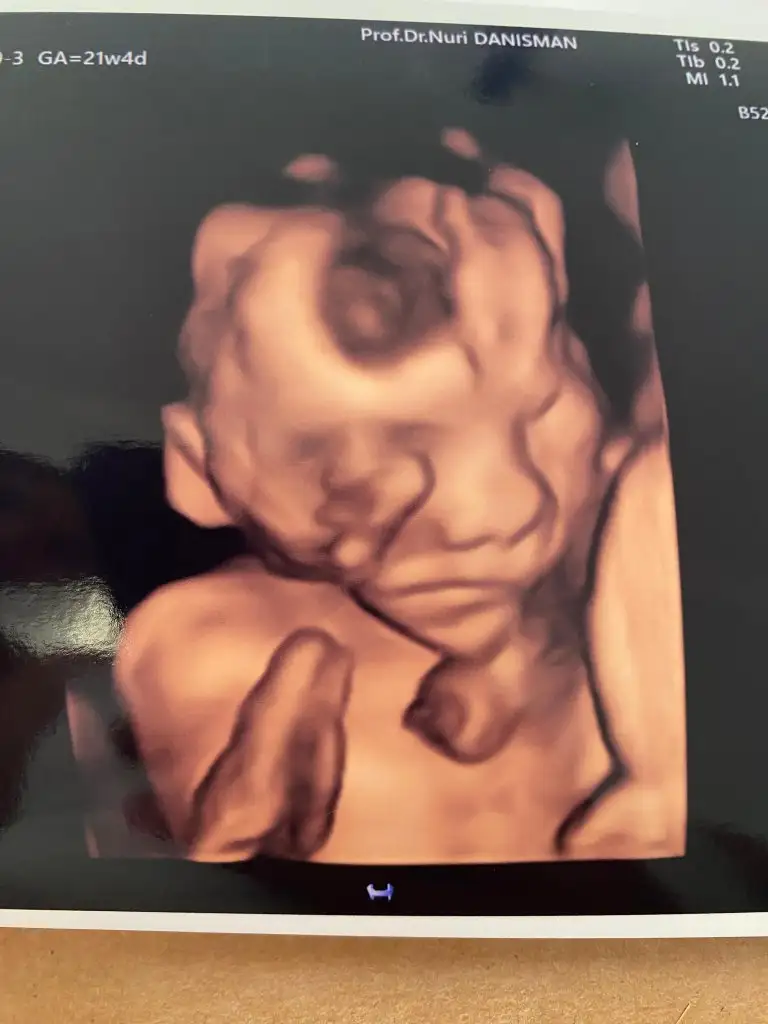

Maşallah canım rabbim sağlıkla kucağına almayı nasip etsinMerhaba kızlarBugün detaylı günümüz vardı 21+4tük 25 cm 430 gr çıktık her şey yolunda bir sorun görünmedi çok şükür. 1 saat sürdü Ankarada olanlar için prof. Nuri danışman hocayı öneriyorum. Her şeyi didik didik inceledi bize CD ve resim verdi utangaç oğlusum sürekli yüzünü kapattı ama ucundan bir poz yakaladık